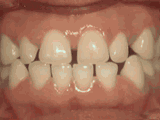

Crowded teeth, certain teeth in abnormal positions, and narrow dental arch result in localized tooth overlap. After extracting one tooth on each side and undergoing orthodontic treatment, the result can be as follows: